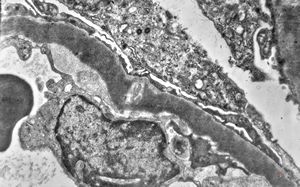

M,17y. | Alport syndrome - split and laminated basement membranes